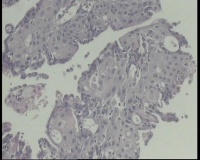

镜下见子宫内膜腺体异型增生,呈乳头状,筛网状排列,细胞核圆形,大小尚均匀,可见少量核分裂像,部分区域鳞化,间质少,部分区域无间质,间质有坏死